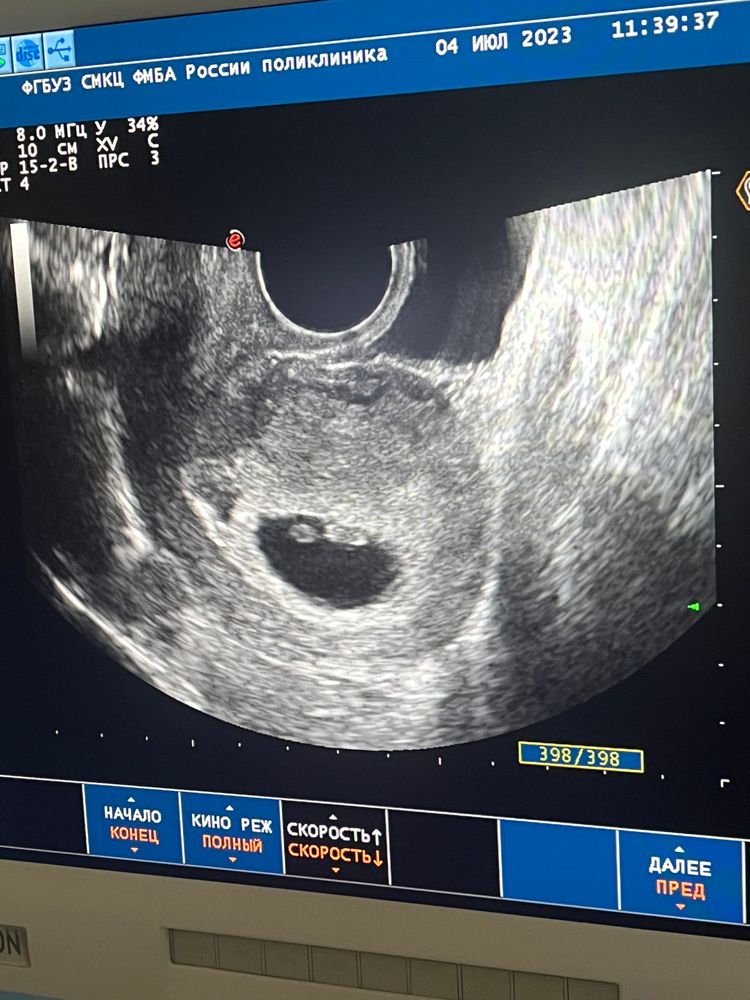

7 недель и 4 дня 💓

Узи 7-8 неделя Варикоз в мало тазу и беременность